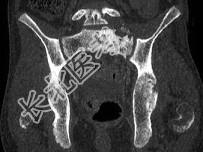

- 单项选择题如图所示,该青少年的最可能的诊断是 ( )

A、尤文肉瘤

B、淋巴瘤

C、软骨肉瘤

D、转移瘤

E、骨肉瘤